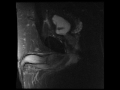

Squamous Cell Carcinoma of the Penis

MRI images demonstrate a T2 dark mass with enhancement arising from the corpora cavernosa of the penis, found to be a squamous cell carcinoma.